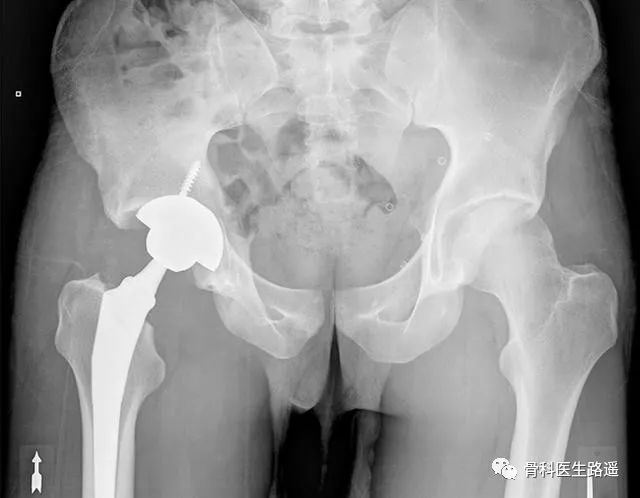

没办法,在他20岁那年,男孩不得不接受右侧全髋置换手术,把自己右边的股骨头和髋臼全部换成了人工假体(术后如下图)。

结果手术后6年来医院复查,男孩右侧手术部位假体整体情况非常好(如下图),左侧股骨头坏死区居然也没有什么变化。